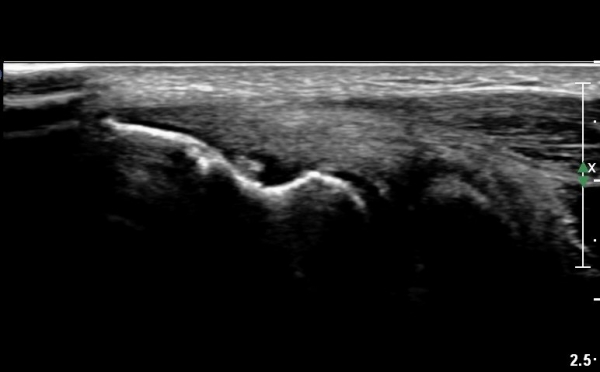

ÁÖµÎ¿Í Á¾´ã¸é°Ë»ç¿Í Ⱦ´Ü¸é°Ë»ç¿¡¼­ ÁֵοͿ¡ ¼ö¾×Àú·ù°¡ °üÂûµÊ(»çÁø 6, 7).